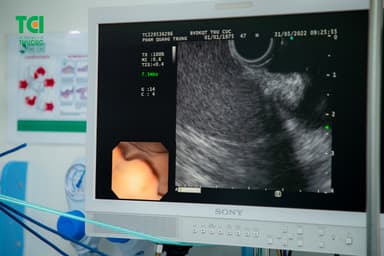

Siêu âm nội soi (EUS) là kỹ thuật chẩn đoán hình ảnh kết hợp giữa nguyên lý siêu âm và nội soi. Bằng cách sử dụng ống nội soi có gắn đầu dò siêu âm tần số cao, phương pháp này cho phép tiếp cận gần nhất vị trí cần thăm dò từ bên trong ống tiêu hóa hoặc trực tiếp vào vùng tổn thương. Nhờ đó, bác sĩ có thể đánh giá được tổn thương xuất phát từ lớp nào, mức độ tổn thương, có xâm lấn hay không, có xuất hiện hạch hay không…

So với nội soi thông thường giúp phát hiện các tổn thương bề mặt, siêu âm nội soi được đánh giá cao hơn nhờ khả năng chẩn đoán cả những tổn thương tại thành ống tiêu hóa, giúp thăm khám các tạng lân cận như: gan, tụy, mật và hướng dẫn các thủ thuật y tế liên quan…

Đặc biệt, khi kết hợp với siêu âm nội soi (EUS), MCU cho thấy ưu thế vượt trội trong đánh giá mức độ xâm lấn, giai đoạn của tổn thương, đặc biệt với những cấu trúc nằm trong thành và dưới lớp niêm mạc ống tiêu hóa nhờ khả năng “nhìn xuyên” từng lớp ở khu vực này. Kết hợp với sinh thiết tức thì, bác sĩ có thể chẩn đoán chính xác tính chất tổn thương tiêu hóa trong vài giờ.